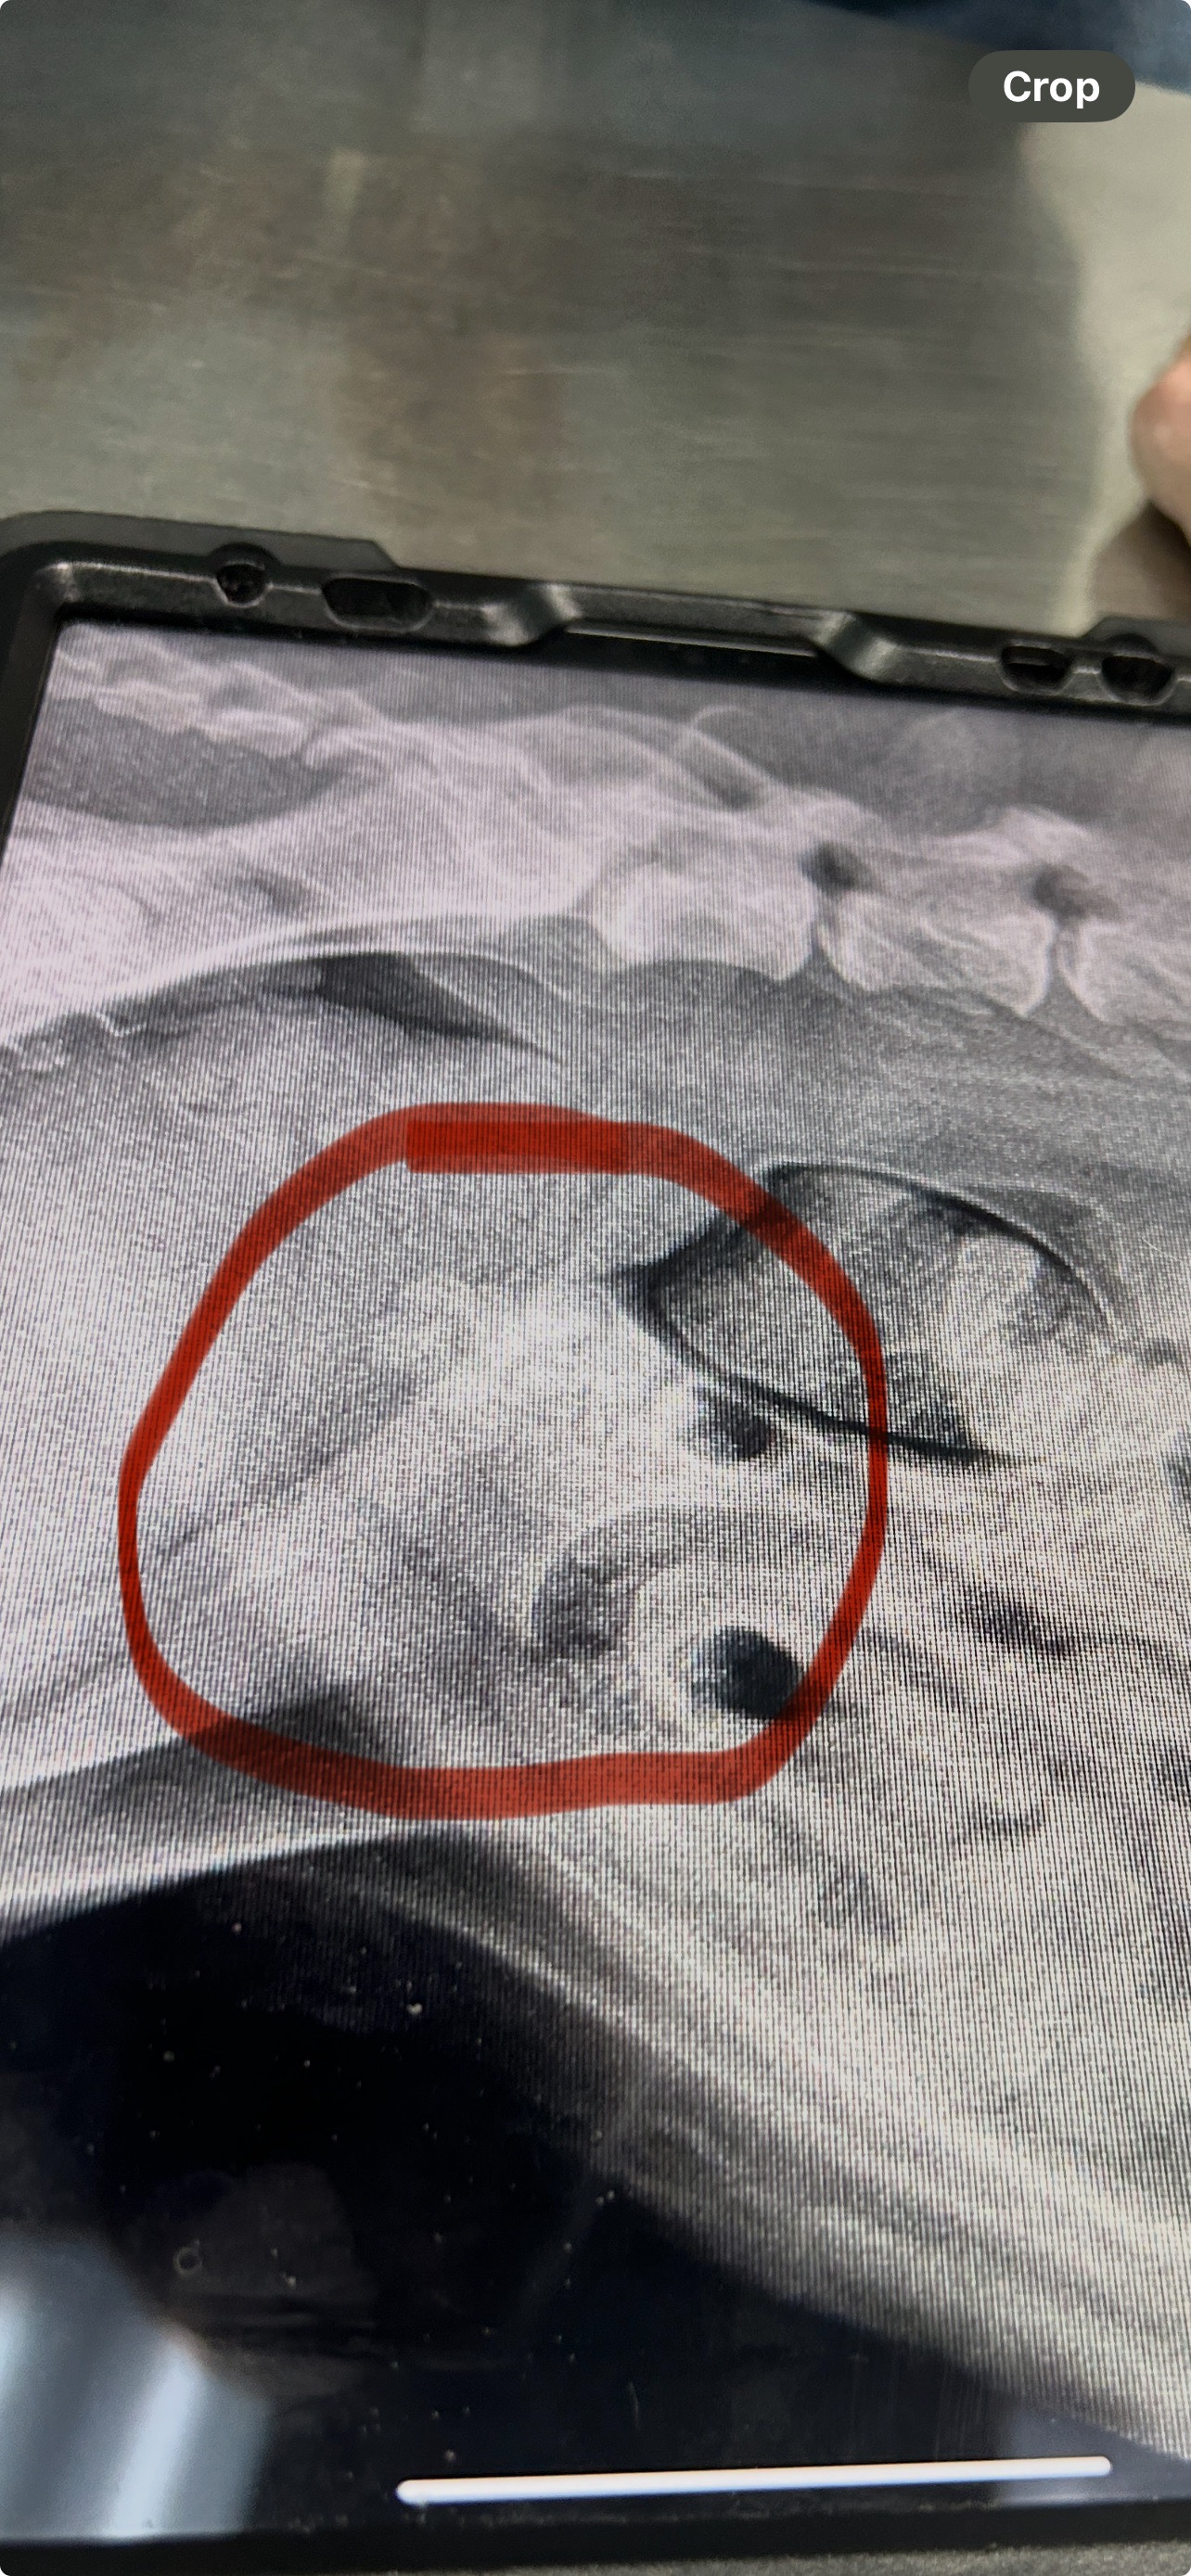

Recently, Mia was diagnosed with multiple kidney stones and urgently needs surgery. Without it, she will continue to be in pain, and her condition could become life-threatening. The cost of the procedure is $3,000 out of pocket, which is more than my family can manage right now.